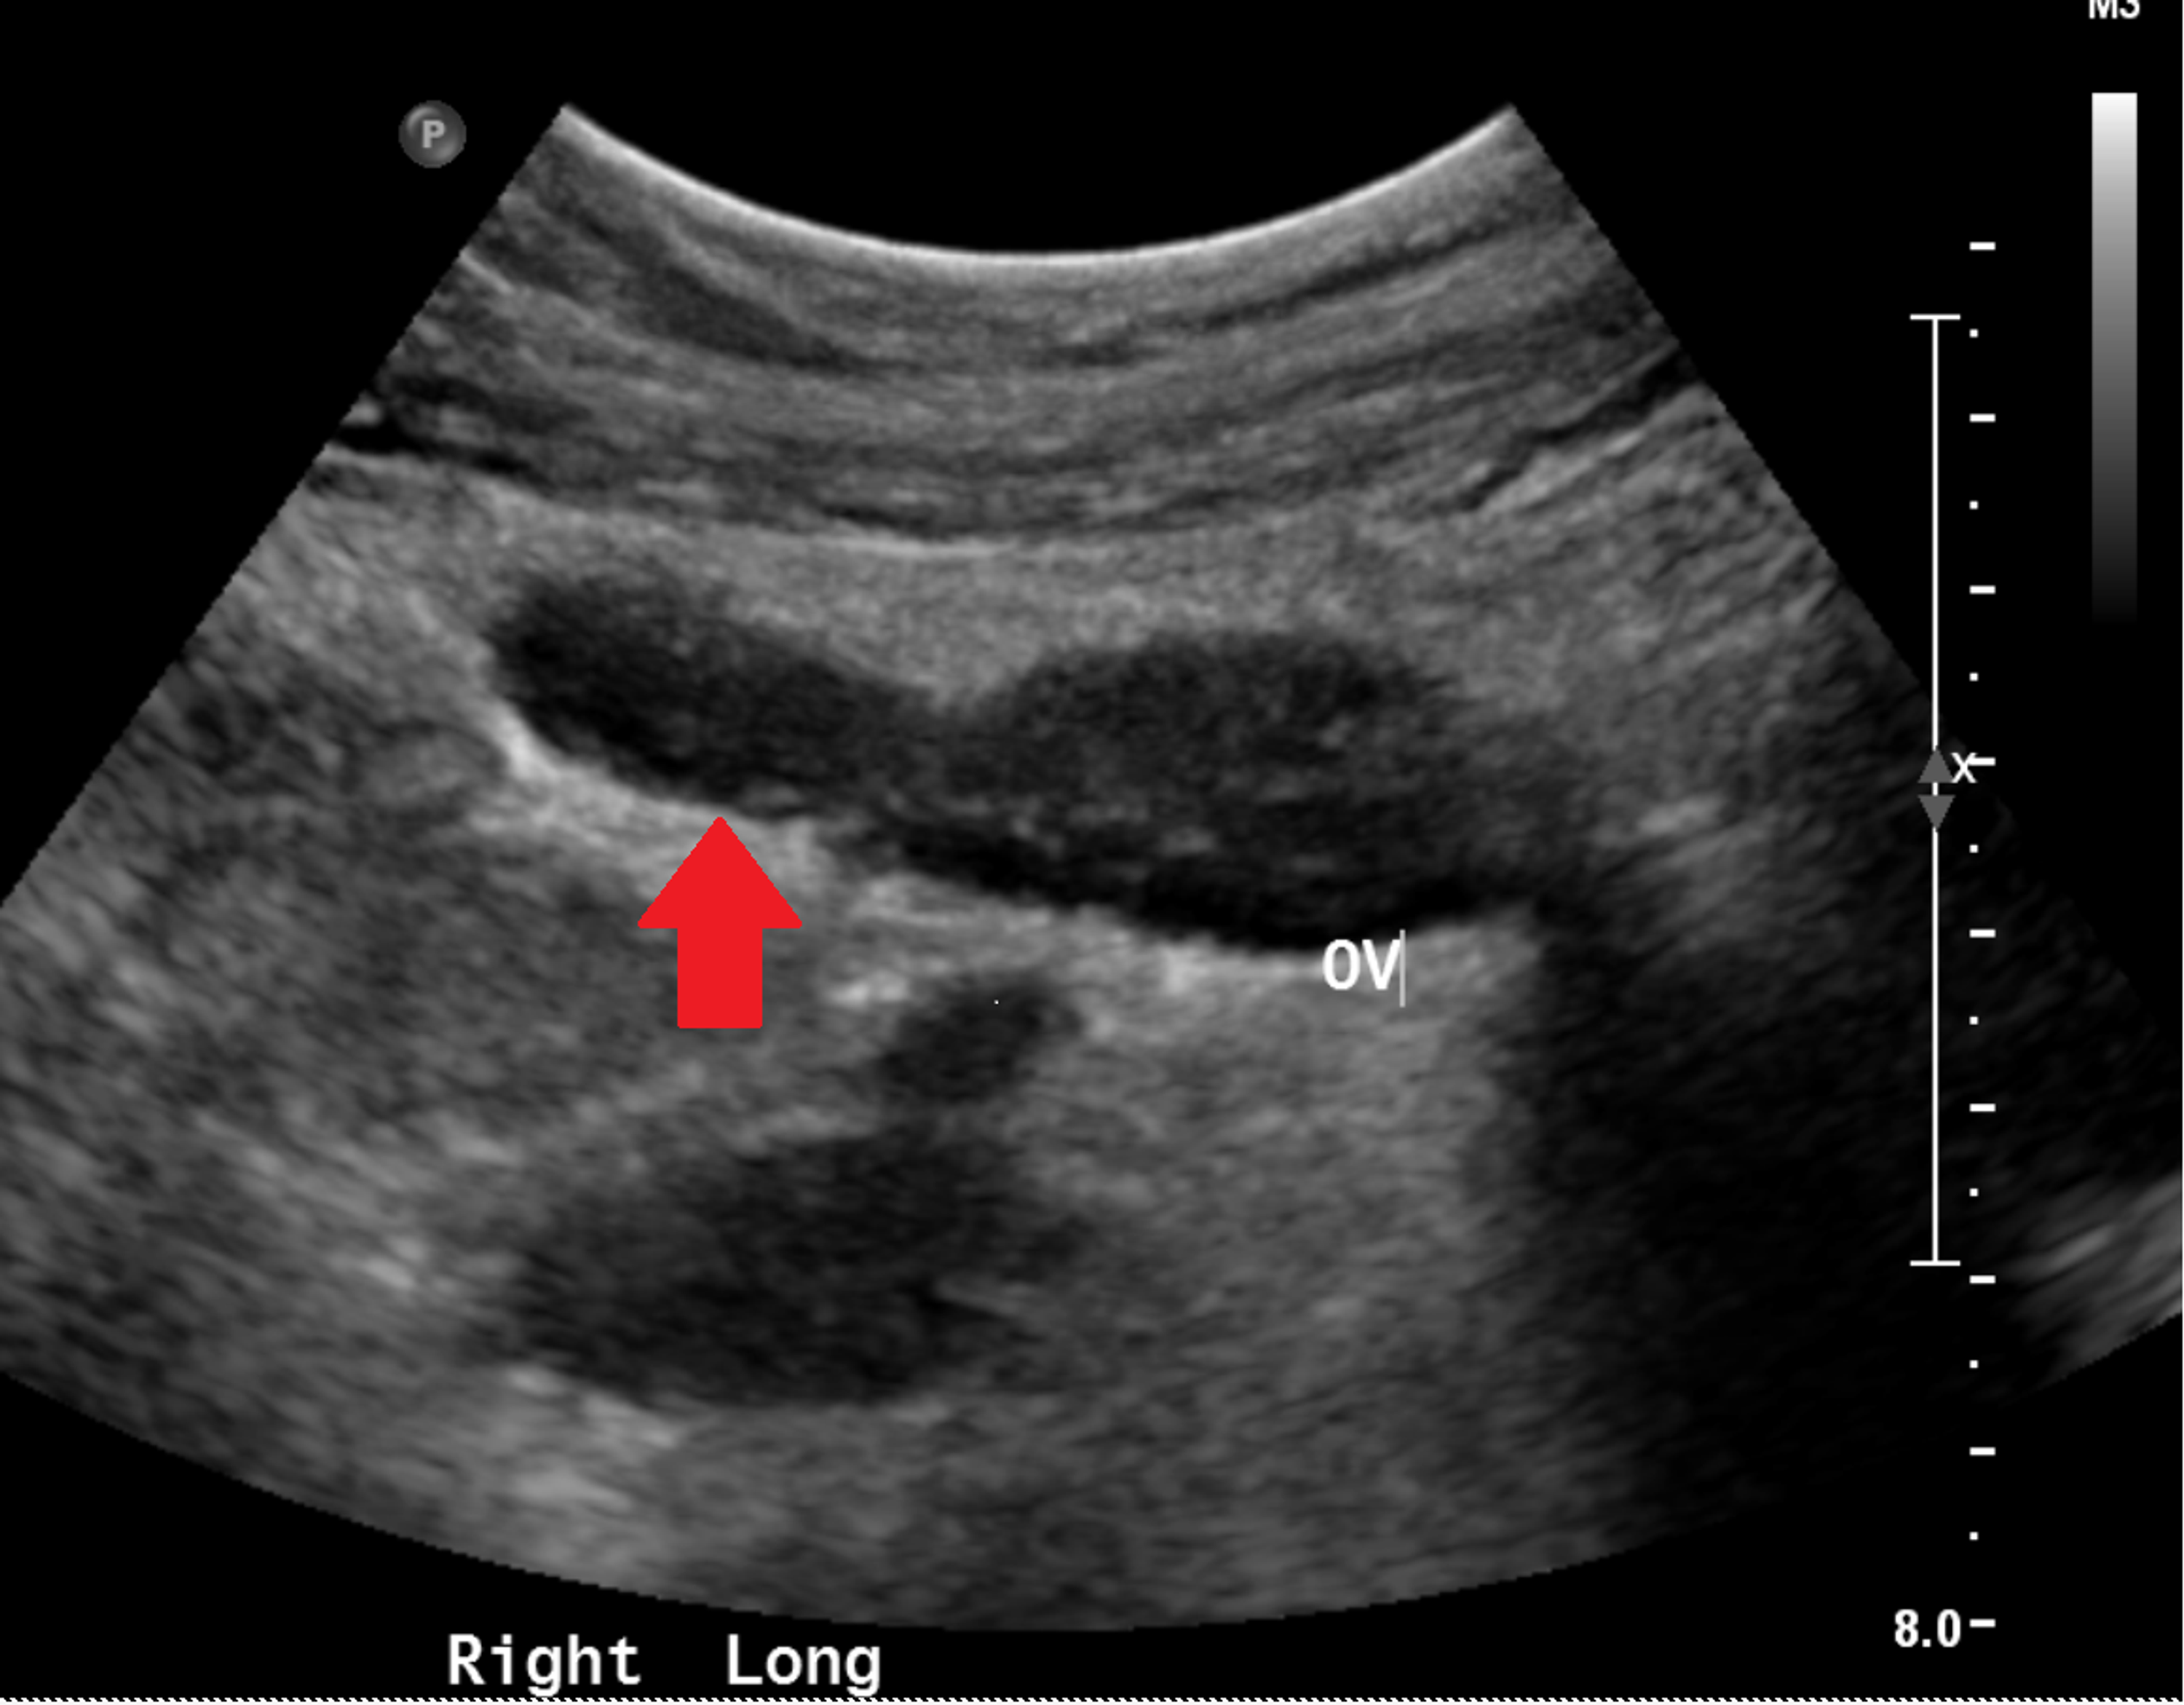

Urachal remnant and a spinning top urethra in a 7yearold female was What Is Spinning Top Urethra 2b) , characterized by dilation of the. It is commonly regarded as. spinning top urethra is a rare deformity, characterised by dilated posterior urethra, more common in young women. It is commonly regarded as. It is seen on vcug as a narrowing of the. spinning top urethra (stu) is a term used to describe a widened posterior urethra. What Is Spinning Top Urethra.